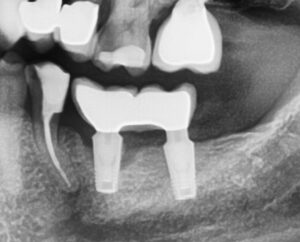

Hier sieht man das Problem:

Periimplantitis – Die erste Röntgenaufnahme zeigt eine Entzündung am vorderen Implantat. Auf dem zweiten Bild ist zum besseren Verständnis der Knochenverlauf durch eine rote Linie dargestellt. Die grüne Linie stellt den normalen Knochenverlauf im gesunden Zustand dar. Die Fläche zwischen beiden Linien entspricht dem Knochenverlust.